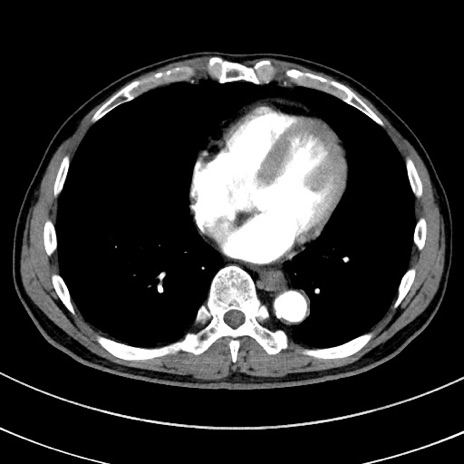

冠状断像

【症例】 60歳代男性

【主訴】 黒色吐物

【現病歴】 4日前から嘔気自覚、2日前の朝食後にも嘔気あり、自分で手で嘔吐反射起こし嘔吐したところ血が混ざっていたため受診。

【既往歴】 5年前汎発性腹膜炎を伴う急性虫垂炎で手術、高血圧、前立腺肥大症、高脂血症

【身体所見】 腹部正中に手術癩痕あり 腹部平坦・軟圧痛なし膨満感あり

【データ】WBC 8400、CRP 4.54